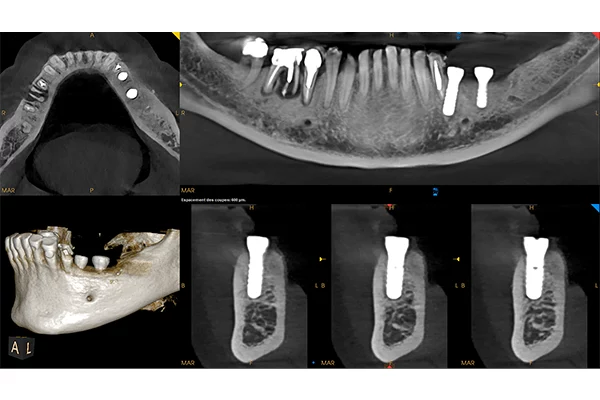

• MAR patentované potlačení artefaktů s živým náhledem efektu filtru pomocí nezávislého algoritmu 3D (zcela unikátní)

• CAD/CAM kompatibilní-skenování otisků a odlitků a převod do stl

• Propojení s optickými stl skeny IO skenerů